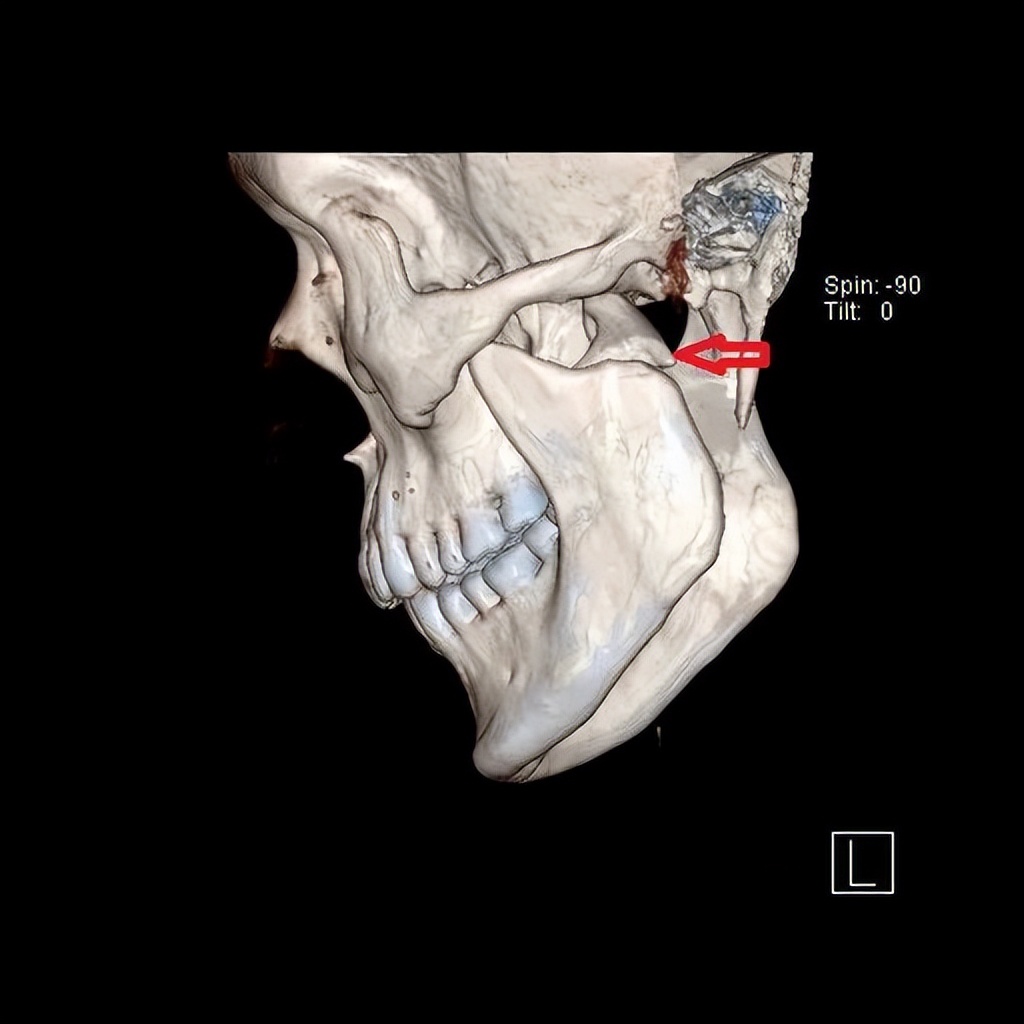

老百姓口中的“下巴”,指的是面部下颌骨区域,医学专业上特指下颌骨前部中份的颏部,俗语也叫“下巴颏子”。颏部因位置突出靠前,受伤瞬间人体反应等因素,该部位容易造成直接损伤,形成软组织裂伤及下颌骨中间部分骨折。然而,由于下颌骨呈马蹄形结构,两侧向上借助升支形成的髁突与颅底结构形成颞下颌关节,如果颏部的直接外力过大,力量沿升支传导向上,就可能造成下颌骨髁突骨折。

术前

髁突骨折较一般下颌骨骨折复杂。首先,髁突参与形成颞下颌关节,该关节是人体最灵活功能最复杂的关节之一,一旦遭受损伤,可能出现咬合紊乱、张口受限、关节强直、关节炎等;由于髁突为生长发育中心,未成年人还可能影响颌面部的发育。其次,髁突骨折分类及相应治疗原则多样,根据骨折高中低位,髁突骨折可简易分为髁头、髁颈、髁基骨折,每种分类又根据移位等情况分为不同亚型,不同分类亚型需正确选择手术适应症,才能达到最佳治疗效果。第三,髁突手术涉及支配面部表情肌的运动神经-面神经,分泌唾液的大腺体-腮腺等重要解剖结构,需熟练掌握手术技巧,以避免面瘫等影响患者美观的并发症。

淄博市中心医院口腔颌面外科团队在下颌骨髁突骨折方面积累了较为丰富的治疗经验,近年来不断更新吸收先进治疗理念。近期,团队对多位合并髁突骨折的下颌骨骨折患者,按照标准治疗理念,或行手术治疗,或保守康复治疗,均取得了良好的效果。此外,为解决切口瘢痕影响美观的问题,团队医生积极开展了发际内结合耳屏后缘、耳后切口等美容切口设计,使手术切口更为隐蔽不可见,满足了年轻患者的美观需要。